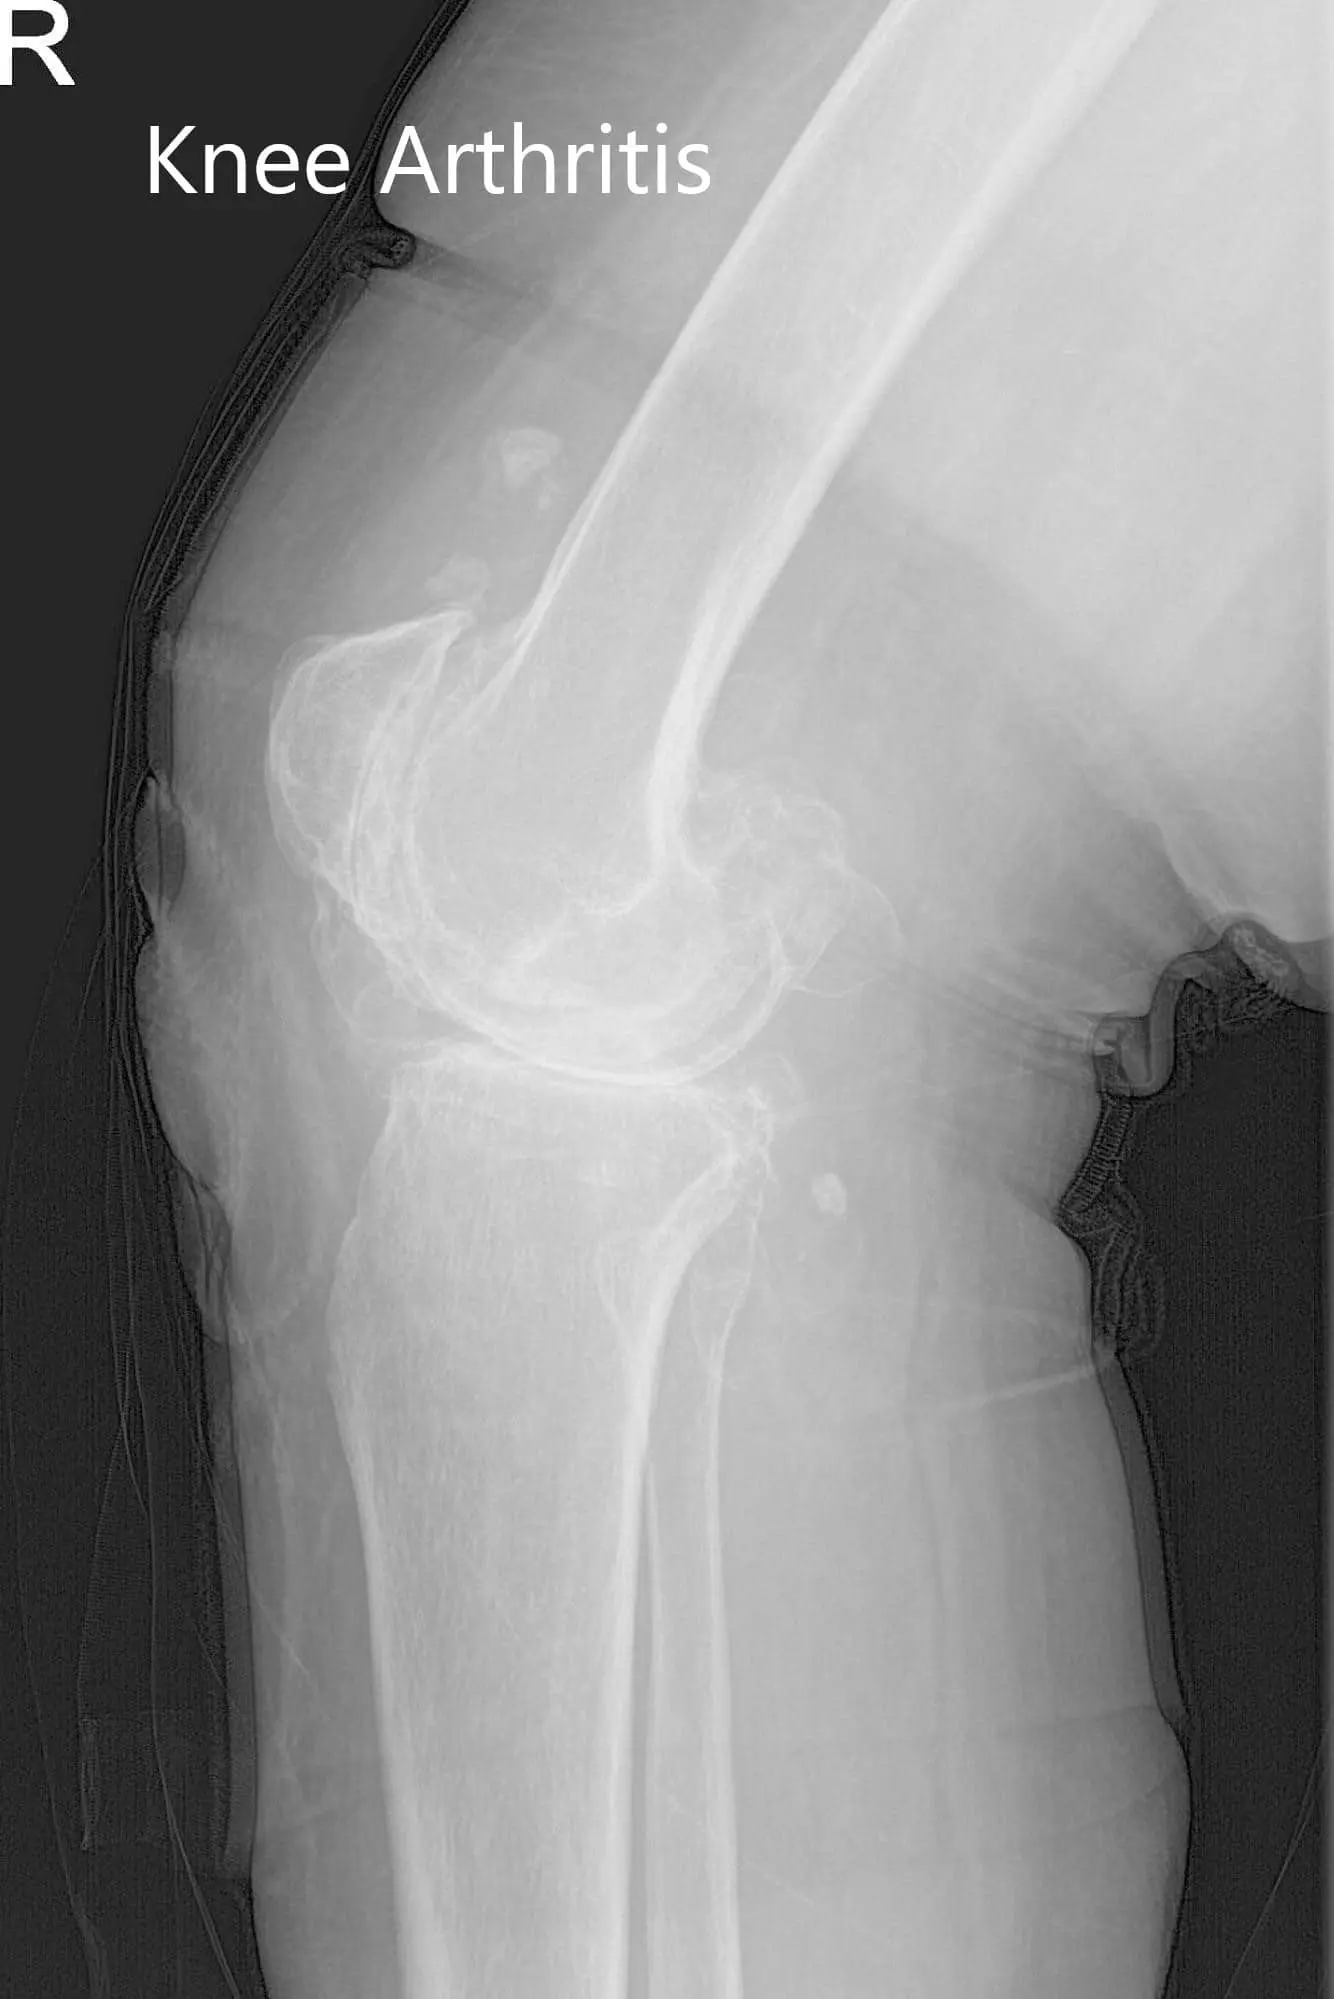

Preoperative X-ray of the right knee showing AP and lateral views